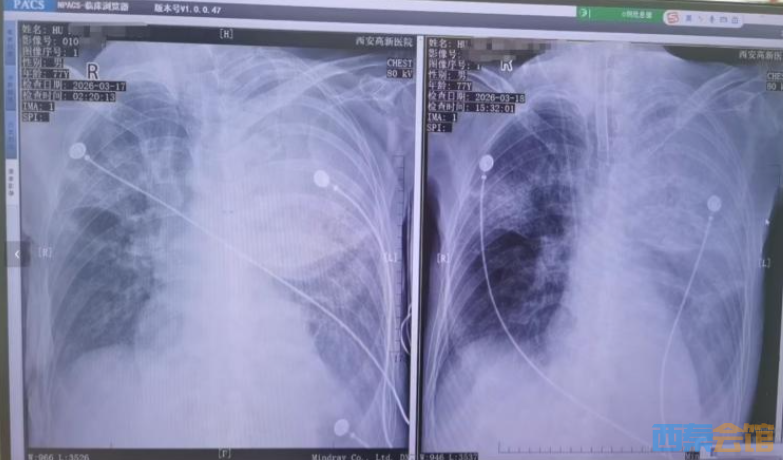

患者接受转院治疗

胡先生说,起初以为是感冒,住院治疗没有效果,还越来越严重,以至于病情危重,“整个肺部全白了”,并且出现呼吸衰竭,医院甚至下了病危通知书。3月17日,家人赶紧将父亲转院到西安高新医院抢救,到医院以后就住进了ICU。经检查,才发现是鹦鹉热衣原体感染导致的重症肺炎。胡先生提供的一份《西安高新医院诊断证明》显示,胡先生的父亲3月17日以重度肺炎入院。诊断为重症肺炎(鹦鹉热衣原体感染)I型呼吸衰竭,急性呼吸窘迫综合征,脓毒症等。

患者胸片